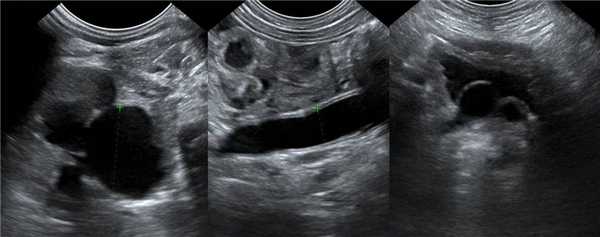

Рисунок. У новорожденного на УЗИ почек определяется гидронефроз (1) и расширенный мочеточник (2) справа. В мочевом пузыре двустороннее уретероцеле (3). При исследовании левой почки структурных изменений не выявлено.

Рисунок. На УЗИ определяется удвоенная чашечно-лоханочная система, расширена лоханка верхнего сегмента (1) и мочеточник на всем протяжение (2, 3), в мочевом пузыре уретроцеле (4). Полное или неполное удвоение чашечно-лоханочной системы возможно увидеть с помощью КТ-урографии.

Рисунок. Дистальный отдел мочеточника расширен, в мочевом пузыре анэхогенное образование с тонким и ровным контуром — уретероцеле.